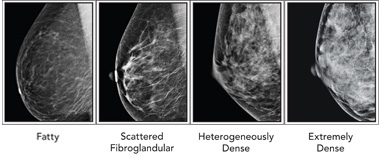

breast dense breasts density birads both mammograms classification google confused doctors patients rads bi non american imaging acsh between